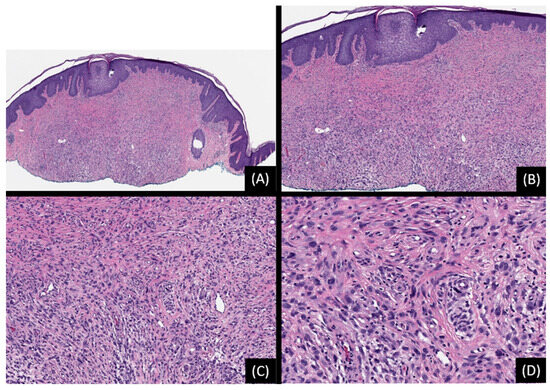

2.3. Spitz Melanoma